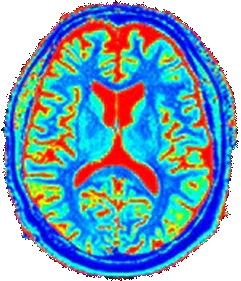

As we age, it's natural for our brain's

communication system to slow down.

The production of key neurotransmitters - like

acetylcholine, the "memory molecule" can

decline.

This can leave our brain cells struggling

to communicate effectively.

Brain at 30 Years

Brain at 60 Years

Average cognitive performance across the lifespan

Many of us feel this as "brain fog" or frustrating "senior moments." We're doing everything right eating well, staying active but our minds still feel a step behind